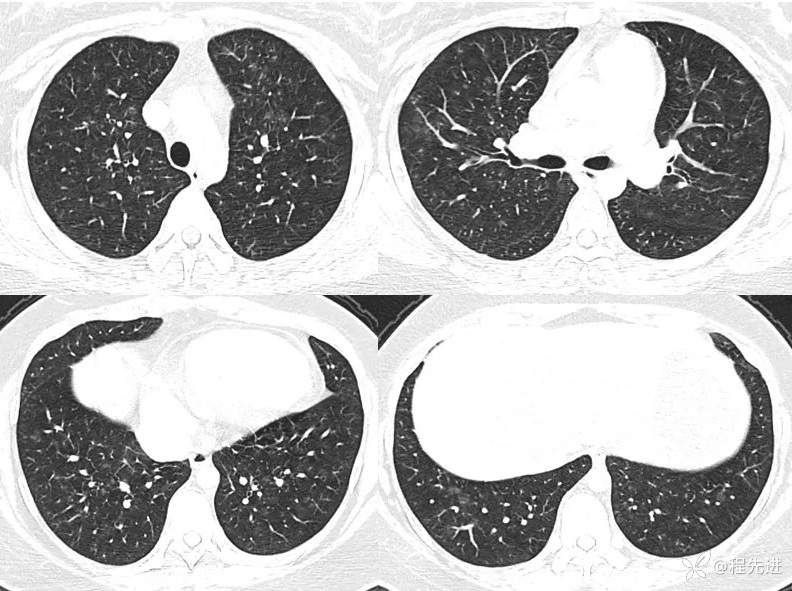

一月余后CT: